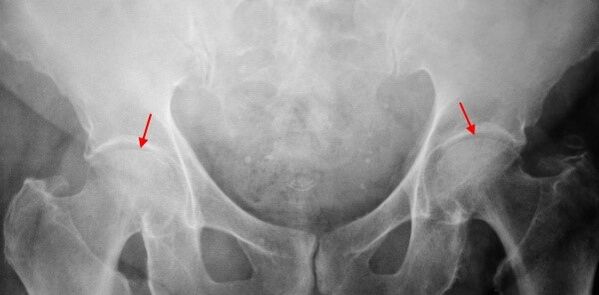

About the X -ray of the patient who suffers from 1st degree thigh, light changes are certain: moderate unequal narrowing of joint gap, as well as bone growths around the outer or internal border of the acetabulum in the absence of head and neck changes of the femur.

In the X -ray images for 2nd degree coxartrosis, a significant unequal narrowing of the joint gap is determined (more than half of the normal height) is determined.The femoral head is slightly moved upward, deformed and increases the size, and its contours become irregular.Bone growths with this degree of coxarthrosis appear not only in the internal, but also on the outer edge of the acetabulum and leaves the cartilage.

About Third Degree Coxarthrosis radiographs, a marked narrowing of the joint gap, a pronounced expansion of the thigh head and several bone growths are detected.

The diagnosis of coxarthrosis is based on clinical signs and data from additional studies, whose main radiography is.In many cases, X -rays make it possible to establish not only the degree of thigh, but also the cause of their occurrence.Thus, for example, an increase in neck diaphysal angle, scenes and acetabulus flattening indicate dysplasia, and changes in the form of the proximal part of the femur are indicated that cOKSARROSIS is a consequence of permanent disease or juvenile episolise.In radiographs of patients with thigh, changes may also be detected indicating lesions.